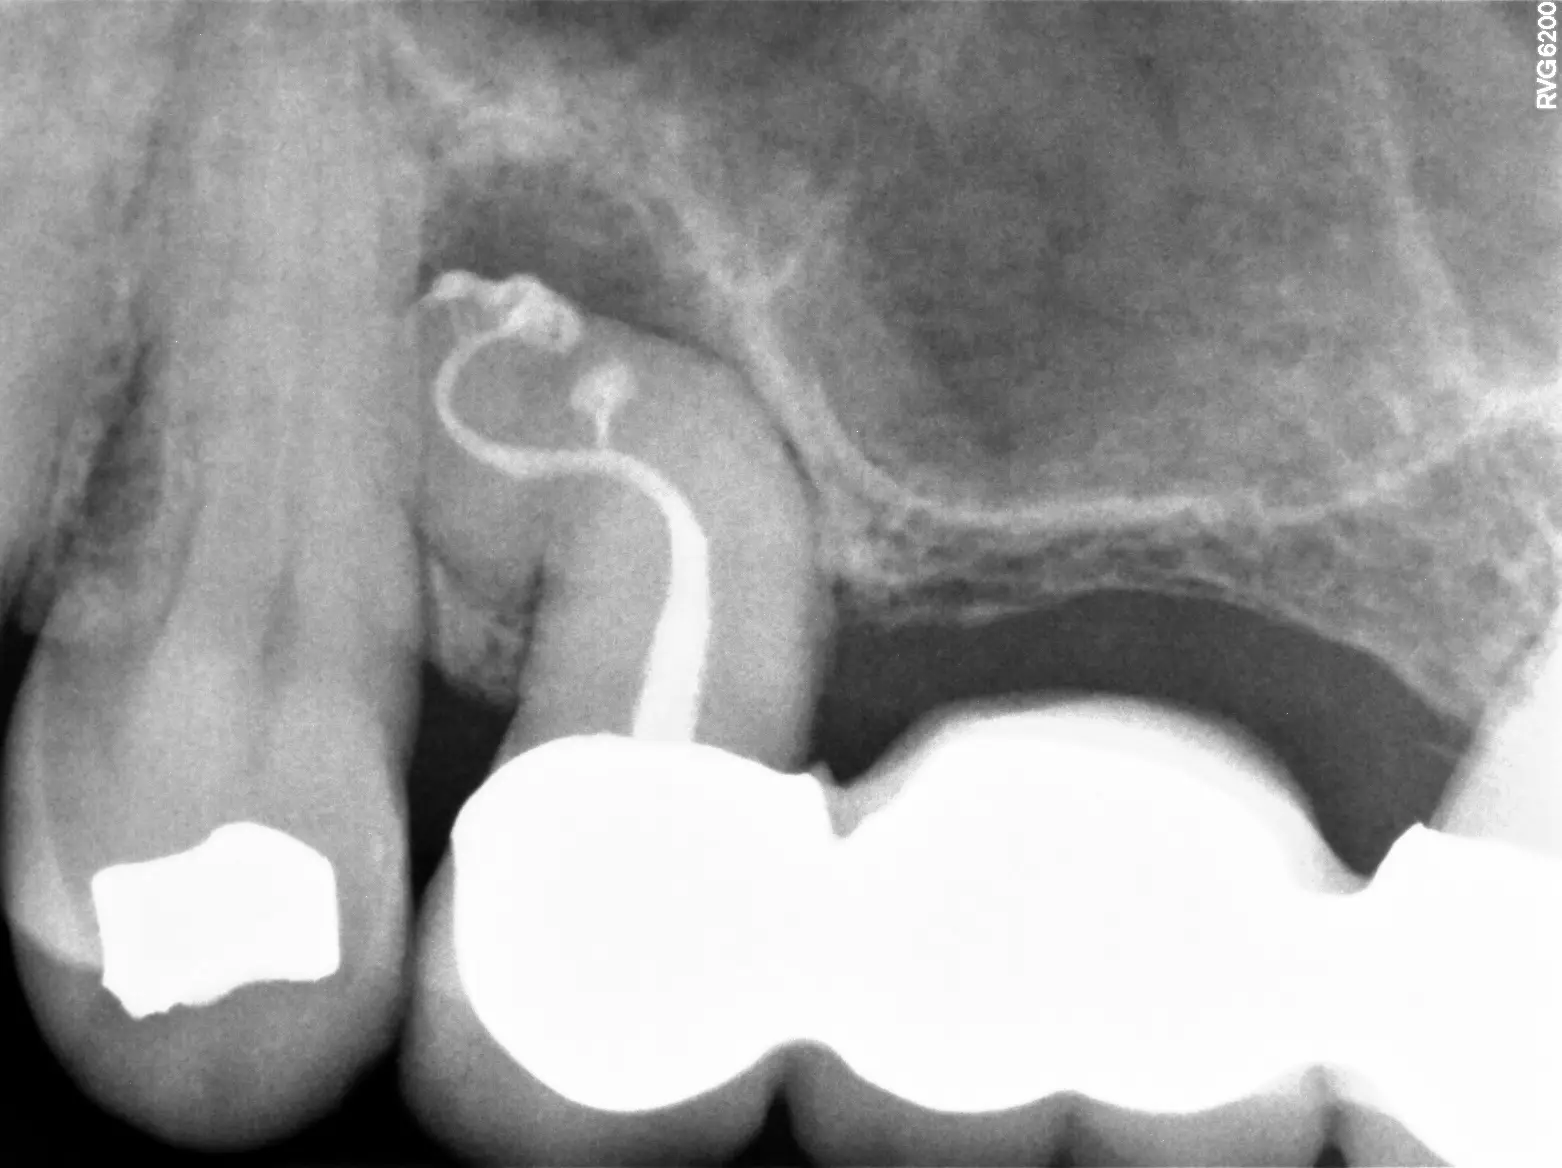

To find the source of your dental pain, your endodontist will begin by performing a comprehensive exam and review of your x-rays to get a complete picture of your oral health. If your tooth is infected, they will determine the extent of the infection to decide if root canal therapy will be an effective treatment.

Conventional root canal therapy usually takes between 30-90 minutes to complete. The anatomy of your tooth, status of the pulp, and any existing materials inside your tooth can affect the time of treatment. In rare cases, treatment will be divided into two separate appointments depending on the extent of infection. In the two- to four-week interim, a medication is placed in your tooth to kill bacteria, relieve pain, and prepare the tooth for the final root canal filling.

Your general dentist may have already taken some recent X-rays of your teeth before your visit with us. To arrive at a diagnosis and recommend treatment, we require specific angles of the tooth that can only be obtained with in-house imaging. We will do our best to obtain the images from your referring dentist and compare them to our own, so that we can review the complete picture with you